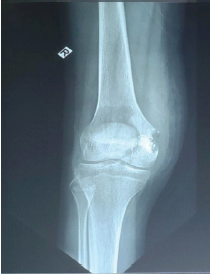

Chronic Flexion Patellar Dislocation with Femoral Patellofemoral Dysplasia and Anterior Bump: Treated by Distal Femoral Subtraction Osteotomy and Medial Patellofemoral Ligament Reconstruction – A Case Report

Florent Francony , Alphonse Daudet Batchom , Sekou Sidibe

………………………………p.245-249